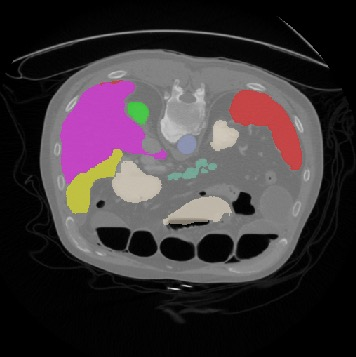

Transformers, the default model of choices in natural language processing, have drawn scant attention from the medical imaging community. Given the ability to exploit long-term dependencies, transformers are promising to help atypical convolutional neural networks (convnets) to overcome its inherent shortcomings of spatial inductive bias. However, most of recently proposed transformer-based segmentation approaches simply treated transformers as assisted modules to help encode global context into convolutional representations without investigating how to optimally combine self-attention (i.e., the core of transformers) with convolution. To address this issue, in this paper, we introduce nnFormer (i.e., Not-aNother transFormer), a powerful segmentation model with an interleaved architecture based on empirical combination of self-attention and convolution. In practice, nnFormer learns volumetric representations from 3D local volumes. Compared to the naive voxel-level self-attention implementation, such volume-based operations help to reduce the computational complexity by approximate 98% and 99.5% on Synapse and ACDC datasets, respectively. In comparison to prior-art network configurations, nnFormer achieves tremendous improvements over previous transformer-based methods on two commonly used datasets Synapse and ACDC. For instance, nnFormer outperforms Swin-UNet by over 7 percents on Synapse. Even when compared to nnUNet, currently the best performing fully-convolutional medical segmentation network, nnFormer still provides slightly better performance on Synapse and ACDC.